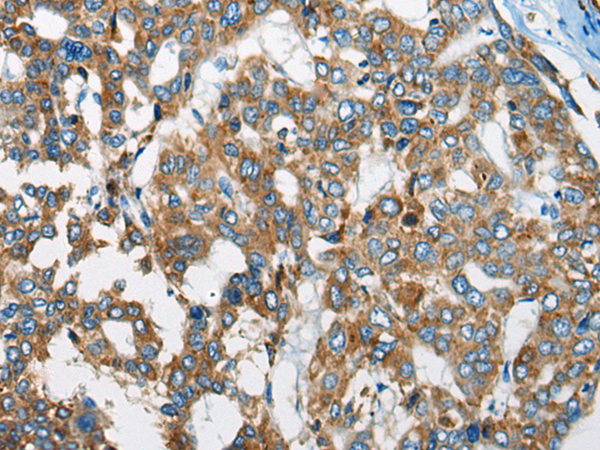

IHC positive control: |

Human liver cancer and human prostate cancer |

IHC Recommend dilution: |

20-100 |